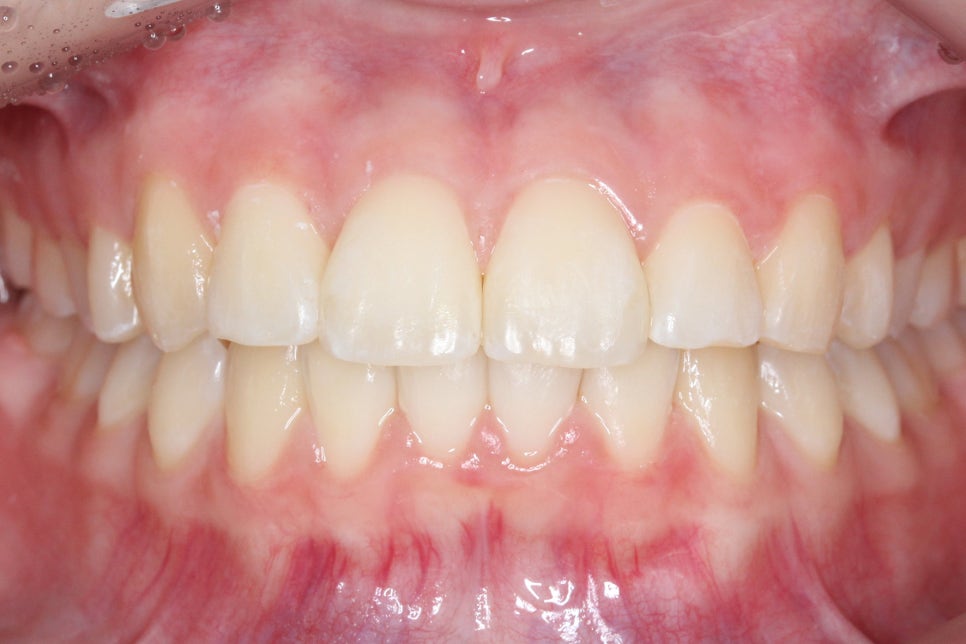

송곳니덧니 교정 후 전치부의 모습입니다.

치료전과 비교해보면 송곳니의 높이가

확연하게 달라진 것을 확인할 수 있는데요,

high canine로 인해 비교적 높은 위치에

맹출되어 있던 견치가 주변 치아들과

조화로운 위치로 교정된 모습입니다.

overbite 모습 역시 교정 후 아랫니가

가지런해지면서 전치부의 crowding이

해소된 모습을 확인할 수 있습니다.

deep bite나 open bite 증상 없이

바르게 교합되는 전치부의 모습이네요^^

2mm정도 덮는 상태가 이상적인 모습입니다.